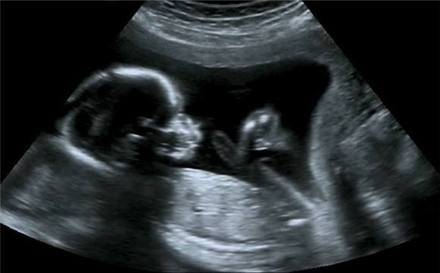

我相信,准妈妈们对于肚子里的新生命都很好奇,我怀孕的时候也是天天想,是男是女啊,长的多大啦,小手小脚在哪里呀,有没有遗传自己的大眼睛啊,等等一系列问题,下面就让我来交大家看懂B超单。

孕中期到晚期,每次B超都会有孩子的生长数据,下面这张图可以很直观的知道各项数据代表了什么。